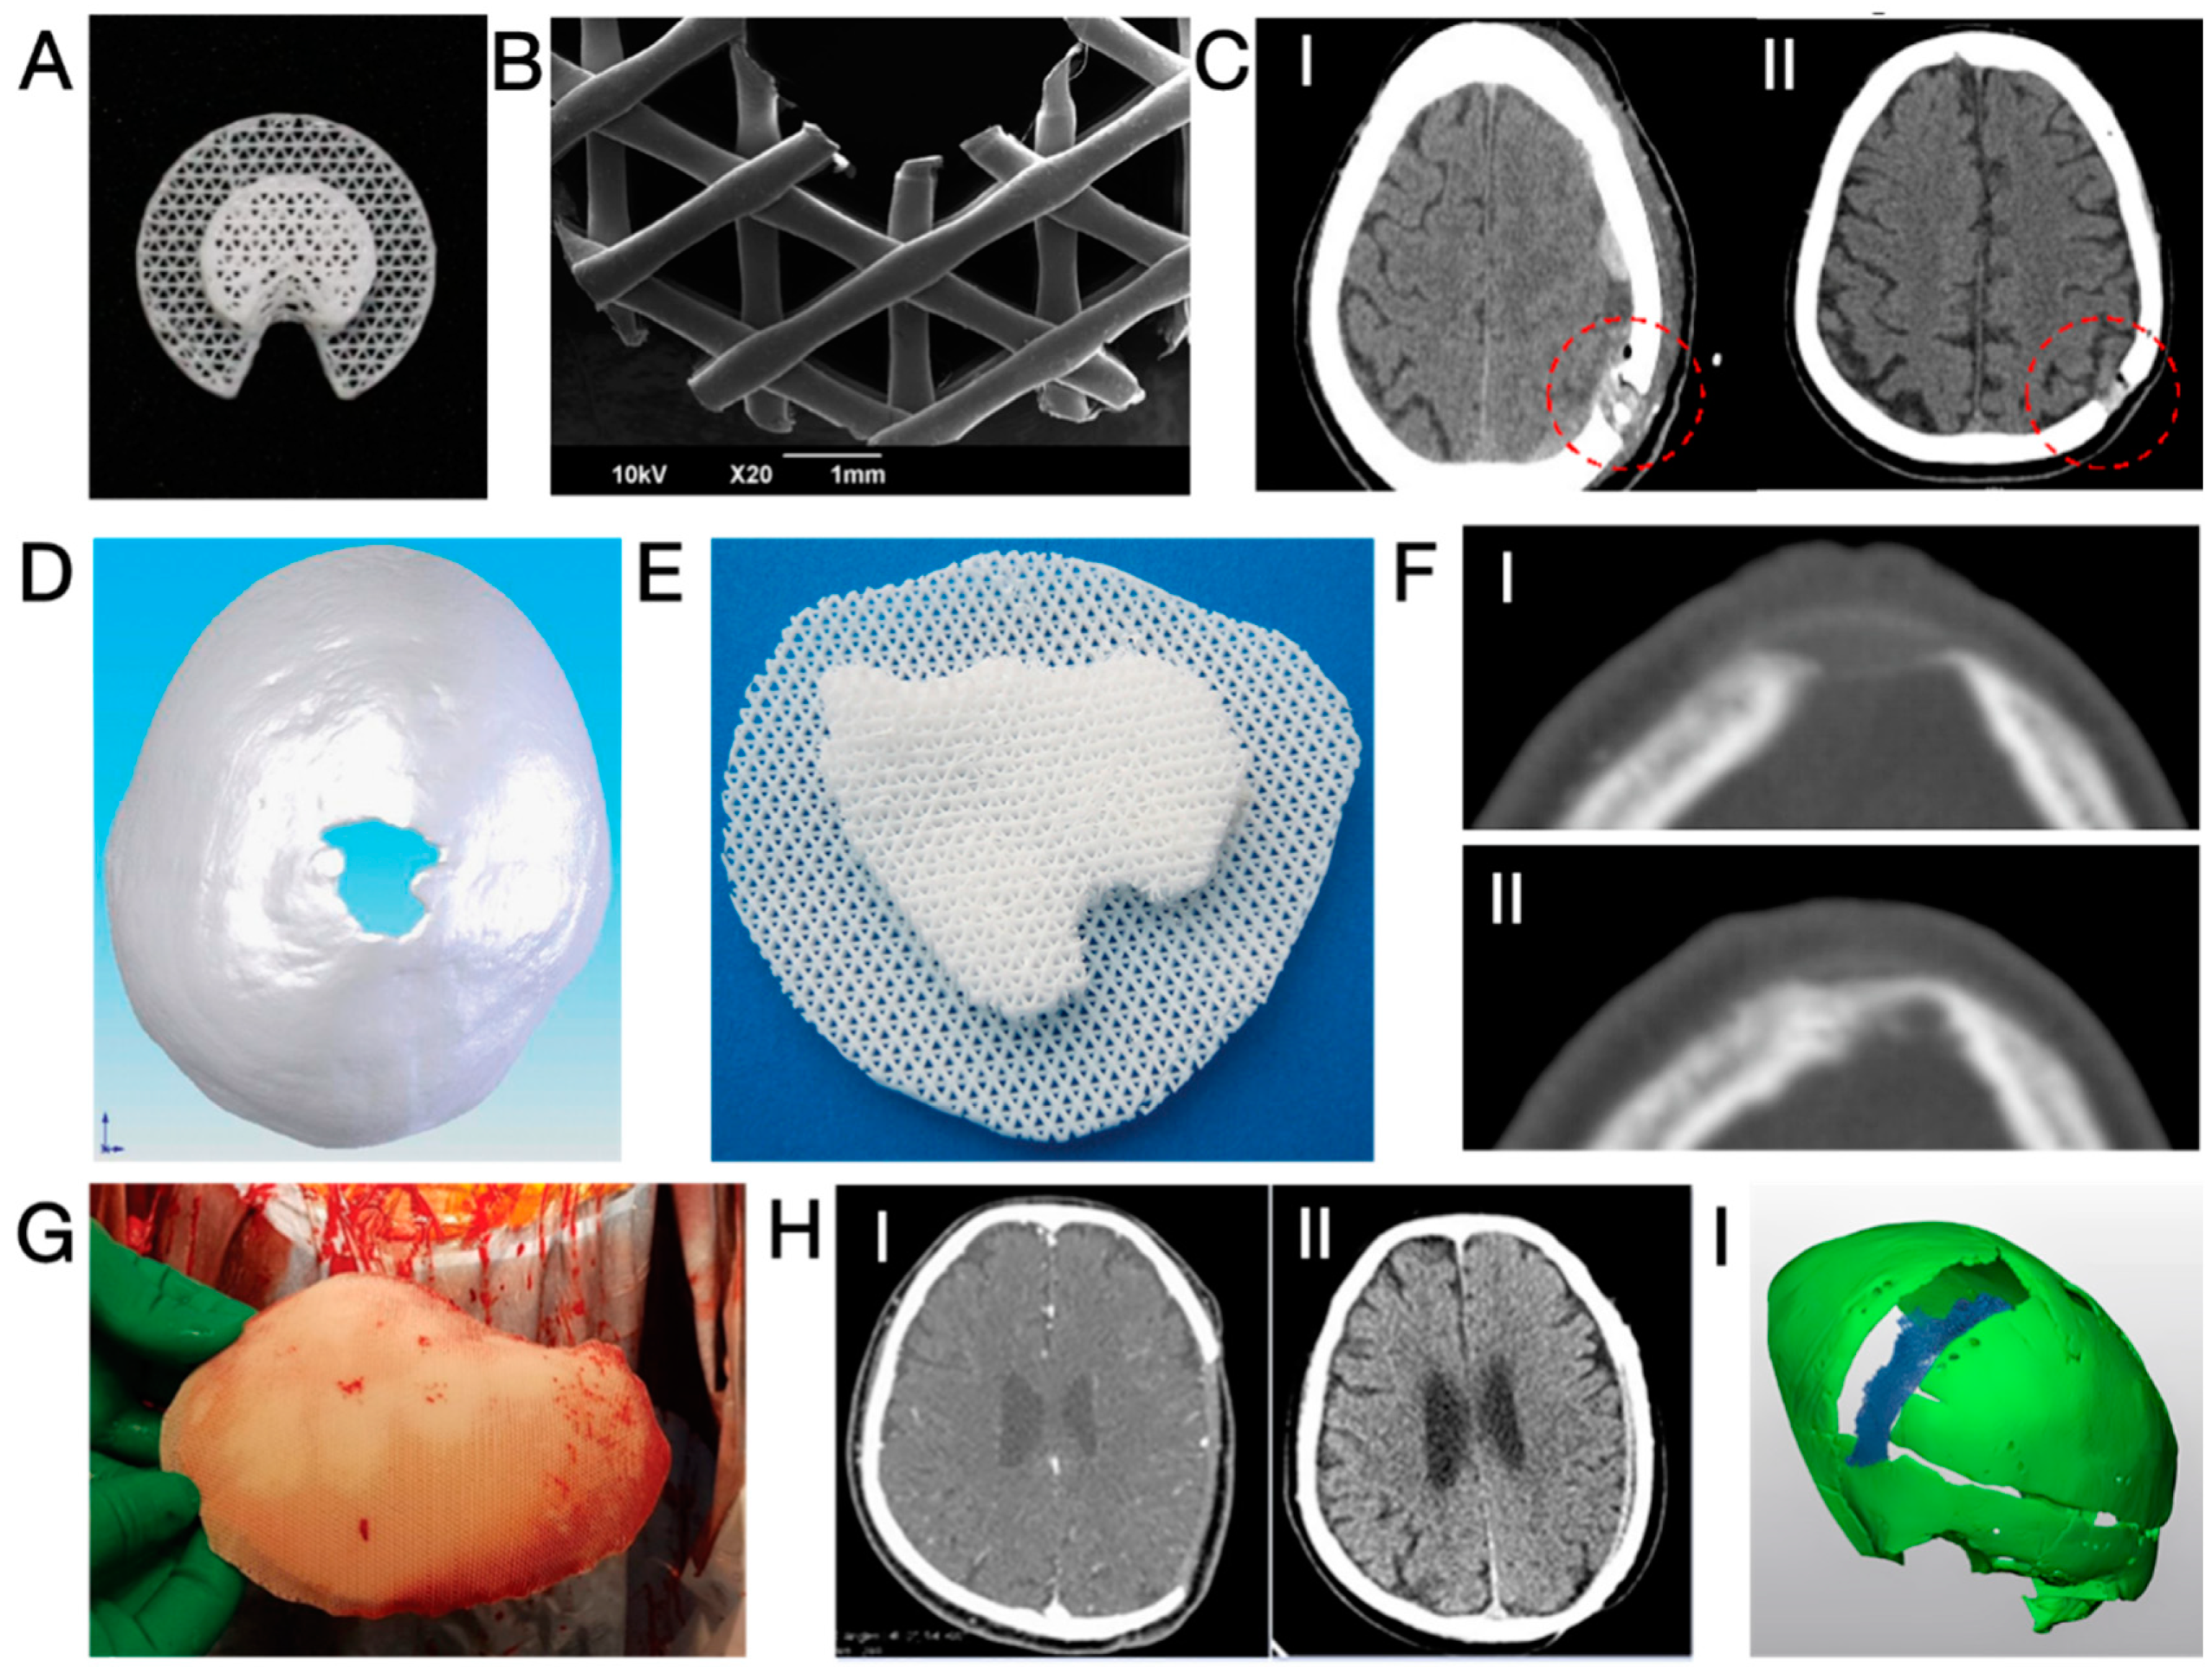

3.1. CaP/Ti Composites

3.3. Three-dimensional-Printed PCL and Its Composites

- Omar, O.; Engstrand, T.; Kihlstrom Burenstam Linder, L.; Aberg, J.; Shah, F.A.; Palmquist, A.; Birgersson, U.; Elgali, I.; Pujari-Palmer, M.; Engqvist, H.; et al. In situ bone regeneration of large cranial defects using synthetic ceramic implants with a tailored composition and design. Proc. Natl. Acad. Sci. USA 2020, 117, 26660–26671. [Google Scholar] [CrossRef] [PubMed]

- Chen, T.; Chen, T.; Zhang, Y.; Zuo, H.; Zhao, Y.; Xue, C.; Luo, B.; Zhang, Q.; Zhu, J.; Wang, X.; et al. Repairing skull defects in children with nano-hap/collagen composites: A clinical report of thirteen cases. Transl. Neurosci. Clin. 2016, 2, 31–37. [Google Scholar] [CrossRef]

- Probst, F.A.; Hutmacher, D.W.; Muller, D.F.; Machens, H.G.; Schantz, J.T. Calvarial reconstruction by customized bioactive implant. Handchir. Mikrochir. Plast. Chir. 2010, 42, 369–373. [Google Scholar] [CrossRef] [PubMed]

- Kihlstrom Burenstam Linder, L.; Birgersson, U.; Lundgren, K.; Illies, C.; Engstrand, T. Patient-Specific Titanium-Reinforced Calcium Phosphate Implant for the Repair and Healing of Complex Cranial Defects. World Neurosurg. 2019, 122, e399–e407. [Google Scholar] [CrossRef]

- Sundblom, J.; Xheka, F.; Casar-Borota, O.; Ryttlefors, M. Bone formation in custom-made cranioplasty: Evidence of early and sustained bone development in bioceramic calcium phosphate implants. Patient series. J. Neurosurg. Case Lessons 2021, 1, CASE20133. [Google Scholar] [CrossRef] [PubMed]

- Lewin, S.; Kihlstrom Burenstam Linder, L.; Birgersson, U.; Gallinetti, S.; Aberg, J.; Engqvist, H.; Persson, C.; Ohman-Magi, C. Monetite-based composite cranial implants demonstrate long-term clinical volumetric balance by concomitant bone formation and degradation. Acta Biomater. 2021, 128, 502–513. [Google Scholar] [CrossRef] [PubMed]

- Engstrand, T.; Kihlstrom, L.; Neovius, E.; Skogh, A.C.; Lundgren, T.K.; Jacobsson, H.; Bohlin, J.; Aberg, J.; Engqvist, H. Development of a bioactive implant for repair and potential healing of cranial defects. J. Neurosurg. 2014, 120, 273–277. [Google Scholar] [CrossRef] [PubMed]

- Engstrand, T.; Kihlström, L.; Lundgren, K.; Trobos, M.; Engqvist, H.; Thomsen, P. Bioceramic Implant Induces Bone Healing of Cranial Defects. Plast. Reconstr. Surg.-Glob. Open 2015, 3, e491. [Google Scholar] [CrossRef] [PubMed]